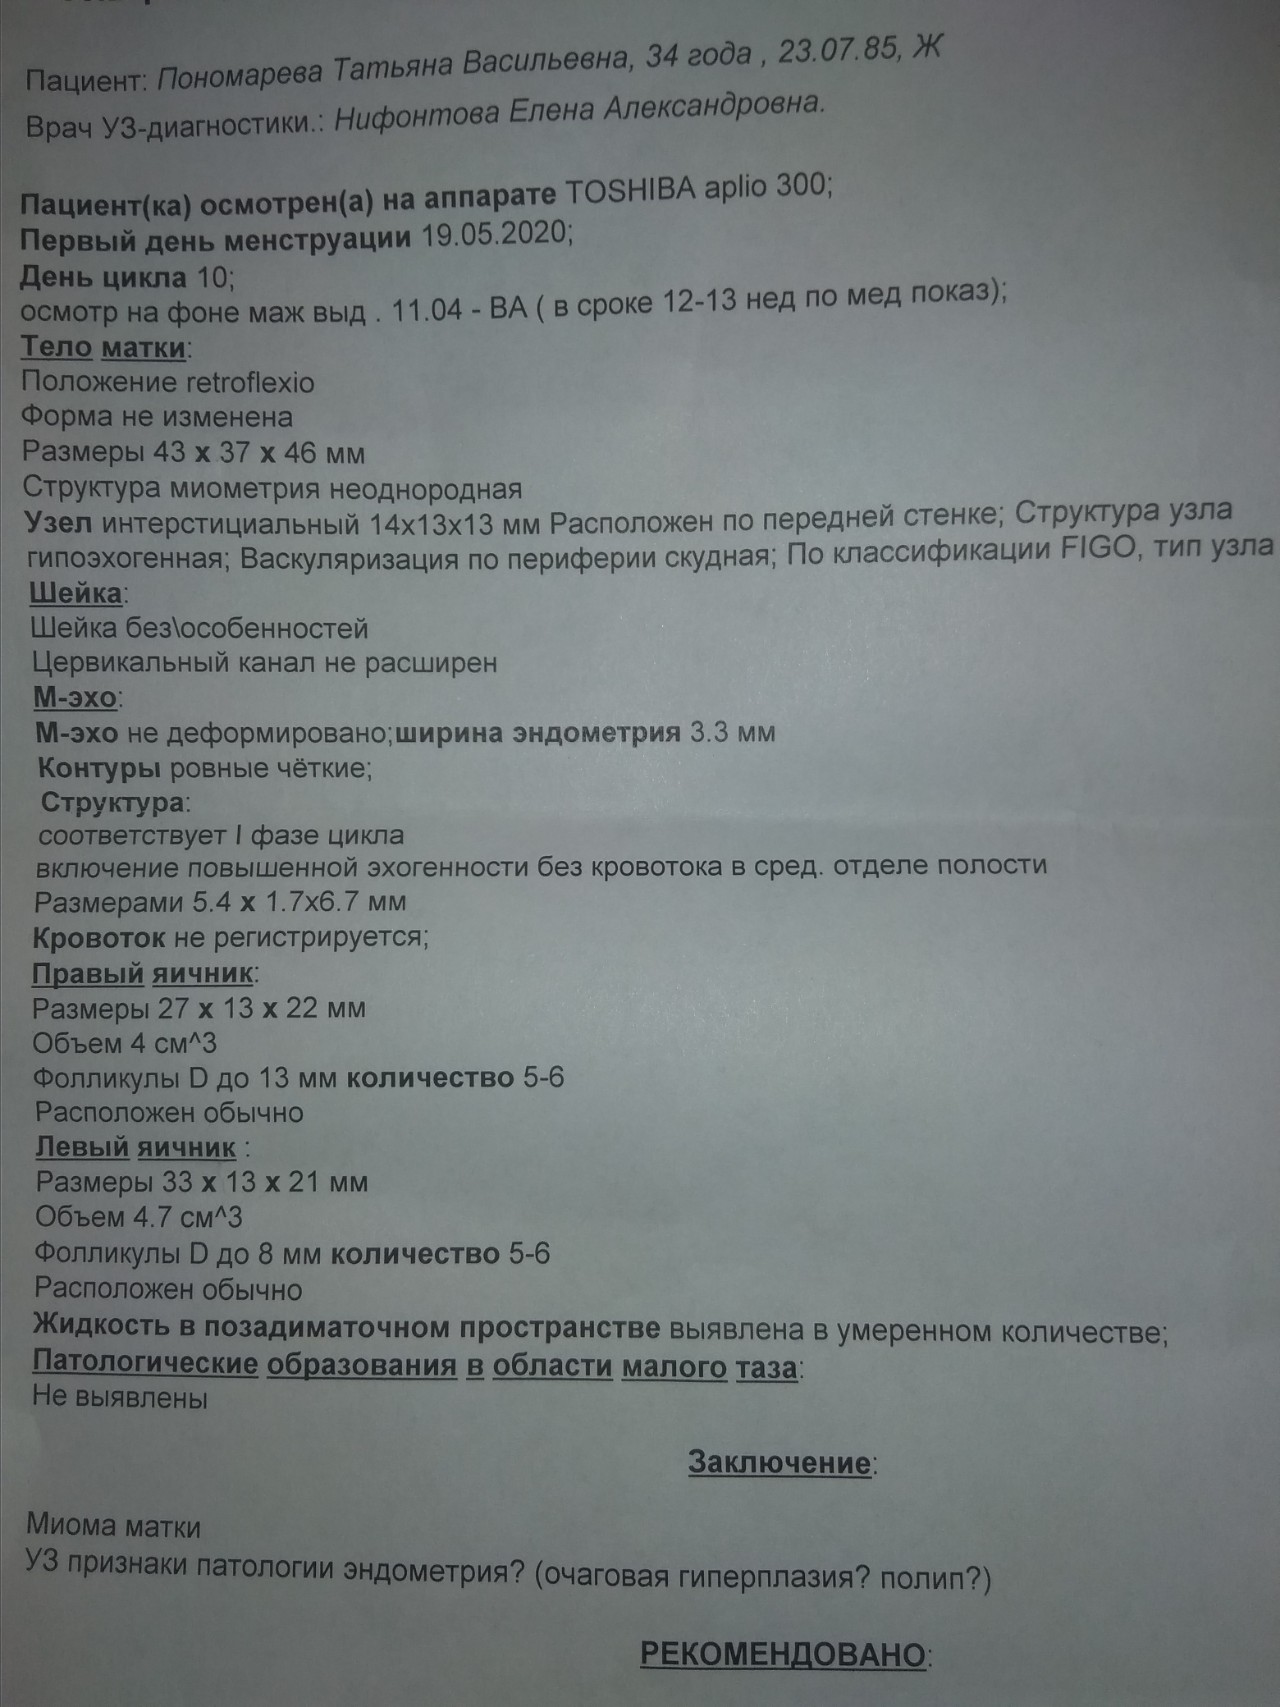

Медицинская диагностика: Гиперплазия эндометрия на УЗИ